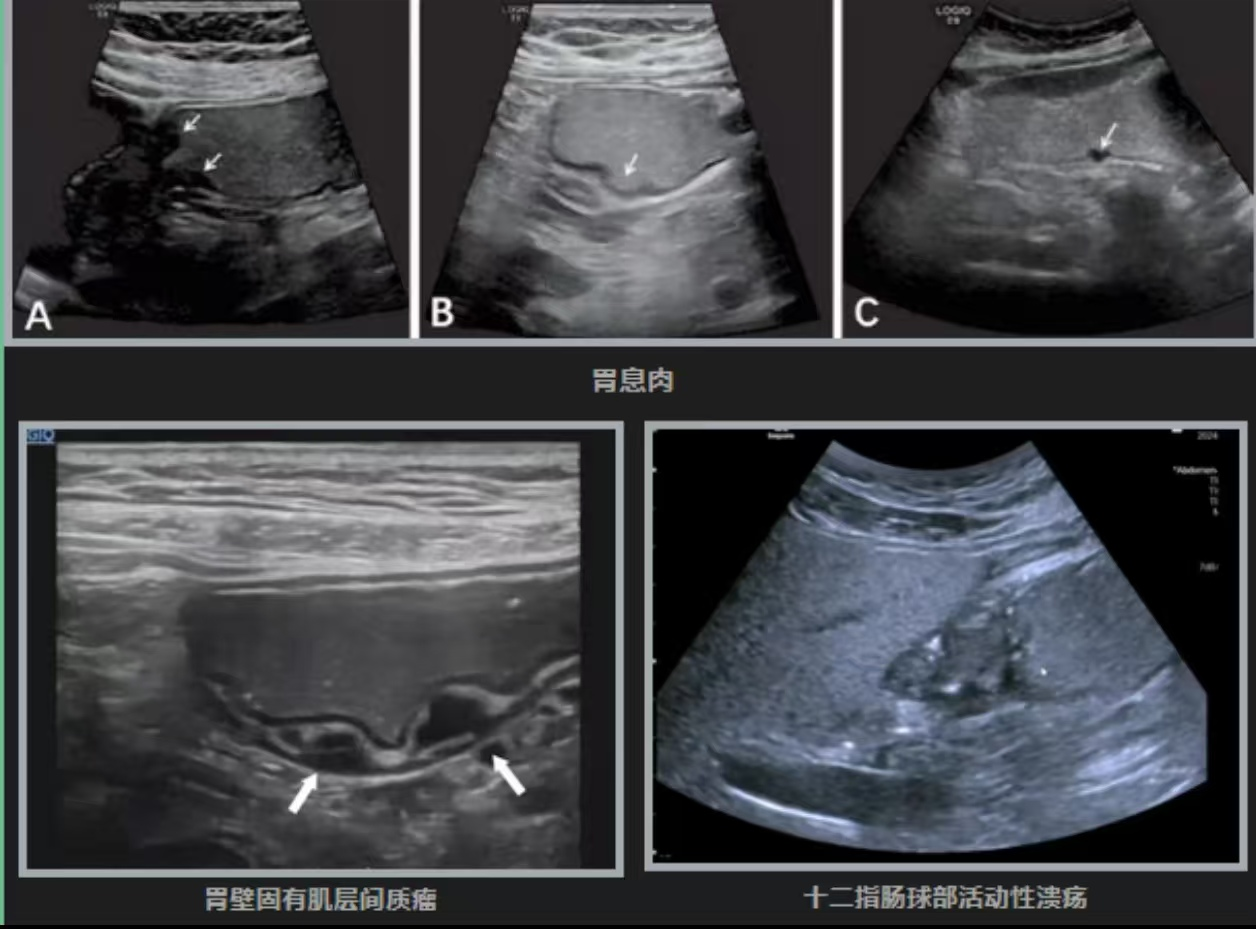

胃肠超声造影检查是通过口服胃肠助显剂充盈胃肠腔,消除胃内及十二指肠腔内气体及粘液的干扰,清晰显示胃腔及胃十二指肠壁的各层次结构,从而进行胃及十二指肠疾病检查。

能清晰观察胃肠壁的黏膜下及肌层病变,如胃间质瘤、平滑肌瘤、胃壁增厚、十二指肠疾病等,这些是普通胃镜容易遗漏的“盲区”。